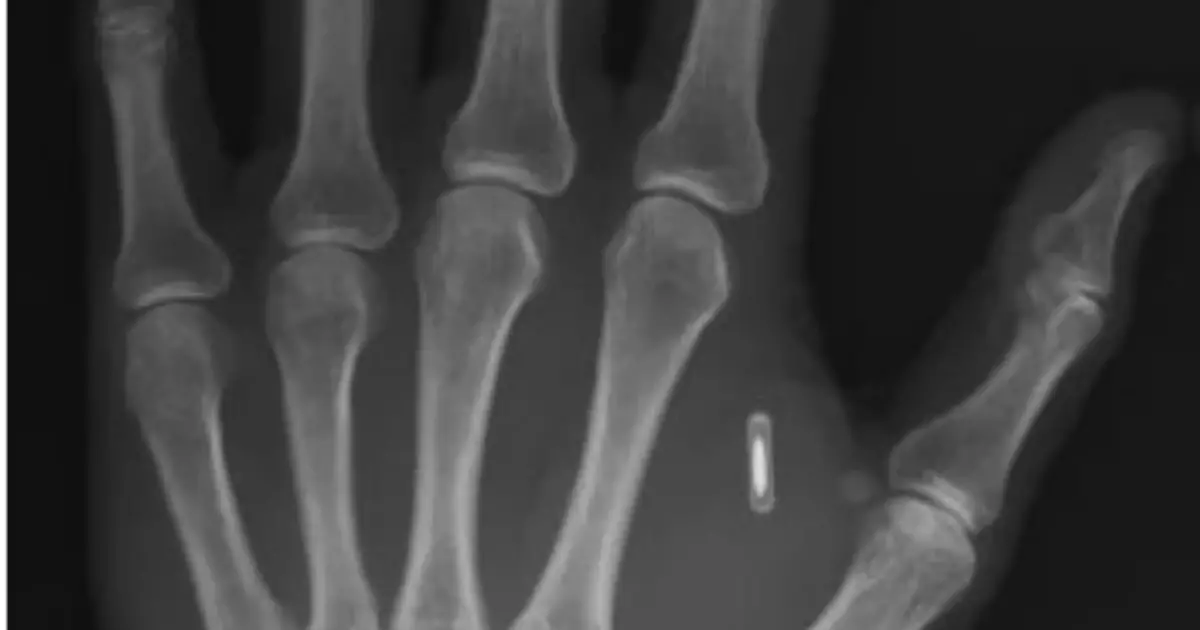

“Mi sono fatto impiantare un chip nella mano per fare trucchi di magia ma ho dimenticato la password”: la storia del mago-scienziato Zi Teng Wang

“Sono tagliato fuori dalla tecnologia dentro il mio corpo, ed è tutta colpa mia“. Zi Teng Wang, prestigiatore e scienziato cinese, si è fatto impiantare un chip RFID nella mano per alcuni trucchi di magia. La mossa a sorpresa si è rivelata controproducente. Wang, infatti, ha scordato la password del chip. Come raccontato su Facebook, […] L'articolo “Mi sono fatto impiantare un chip nella mano per fare trucchi di magia ma ho dimenticato la password”: la storia del mago-scienziato Zi Teng Wang proviene da Il Fatto Quotidiano.